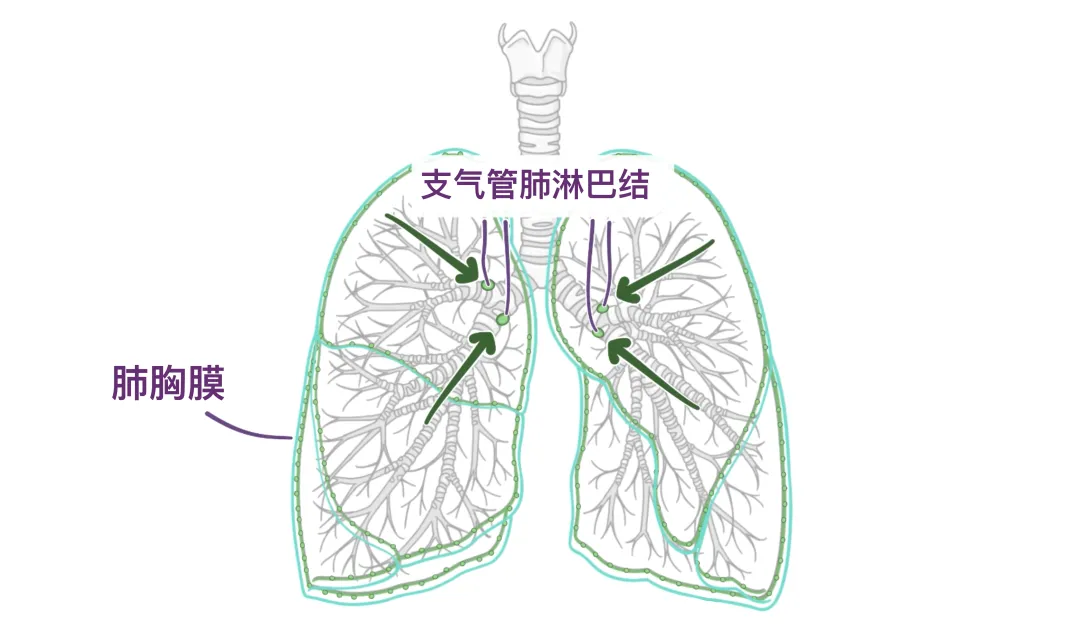

此外,肺还有两个淋巴丛:一个是浅层的,一个是深层的,它们自由地交流。浅层或胸膜下神经丛位于内脏胸膜深处,引流内脏胸膜和肺组织。从这个神经丛流出的淋巴管流入位于肺门区域的支气管肺淋巴结或肺门淋巴结。